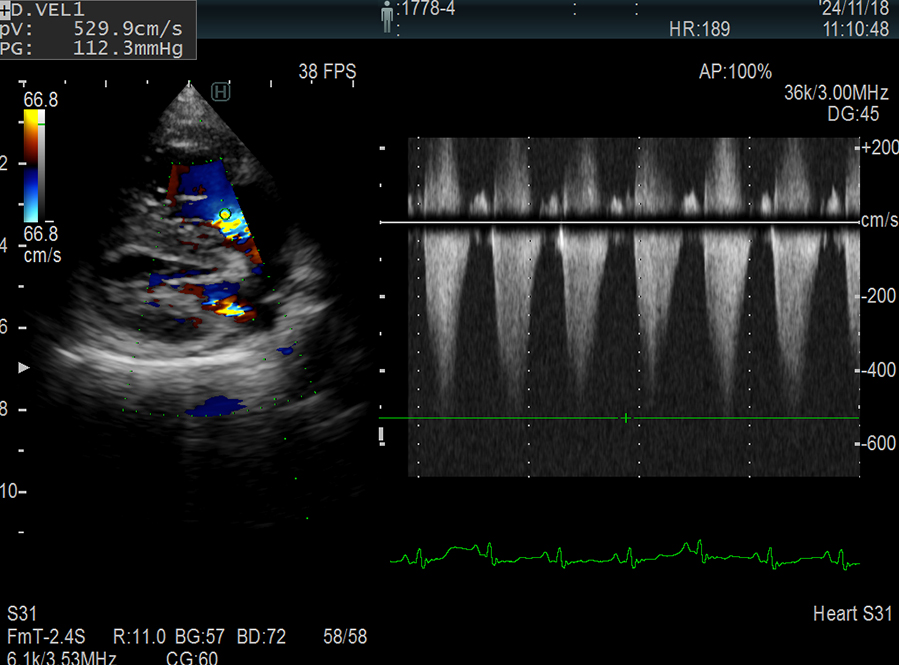

大動脈弁下狭窄(犬)

大動脈弁逆流(犬)

大動脈弁狭窄と逆流(犬)